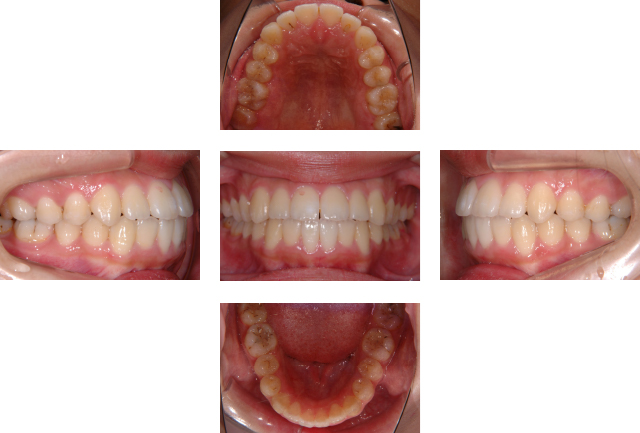

初診時年齢 15歳 主訴 受け口

診断名 反対咬合 装置名 マルチブラケット装置

抜歯の有無 非抜歯 治療期間・

通院回数

約2年半程度・30回

費用の目安 総額 ¥921,800(税込)